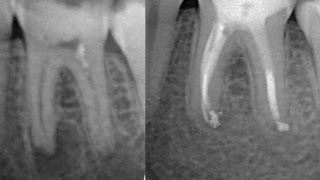

Для диагностики пародонтита важна оценка состояния пародонта, измерение глубины зубных карманов и рентгенография. Лечение включает удаление налета и камней, гигиену полости рта, применение антисептических средств и, в некоторых случаях, хирургическое вмешательство.